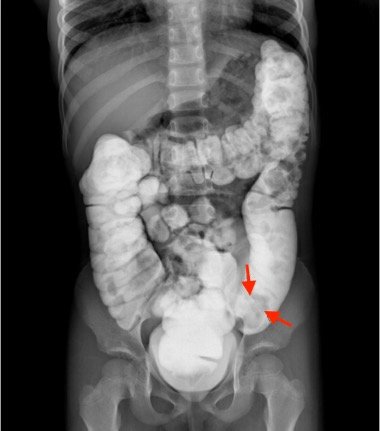

Intussusception is the telescoping of bowel into an adjacent segment of bowel and has an associated risk for bowel ischemia and perforation. The classic triad of abdominal pain, blood in stool, and an abdominal mass is present in less than 40% of pediatric cases and is less common in older children.1 Ultrasound has a high sensitivity and specificity for the diagnosis of intussusception, and once diagnosed, treatment modalities include reduction by either ultrasound or fluoroscopic guided air or hydrostatic enema. The risk of recurrence after successful reduction occurs in up to 12% of pediatric patients and occurs more frequently in older children and children with a pathologic lead point.2 We present a case of a 6-year-old child with colocolic intussusception that was successfully reduced and recurred within five days due to a large colonic polyp.